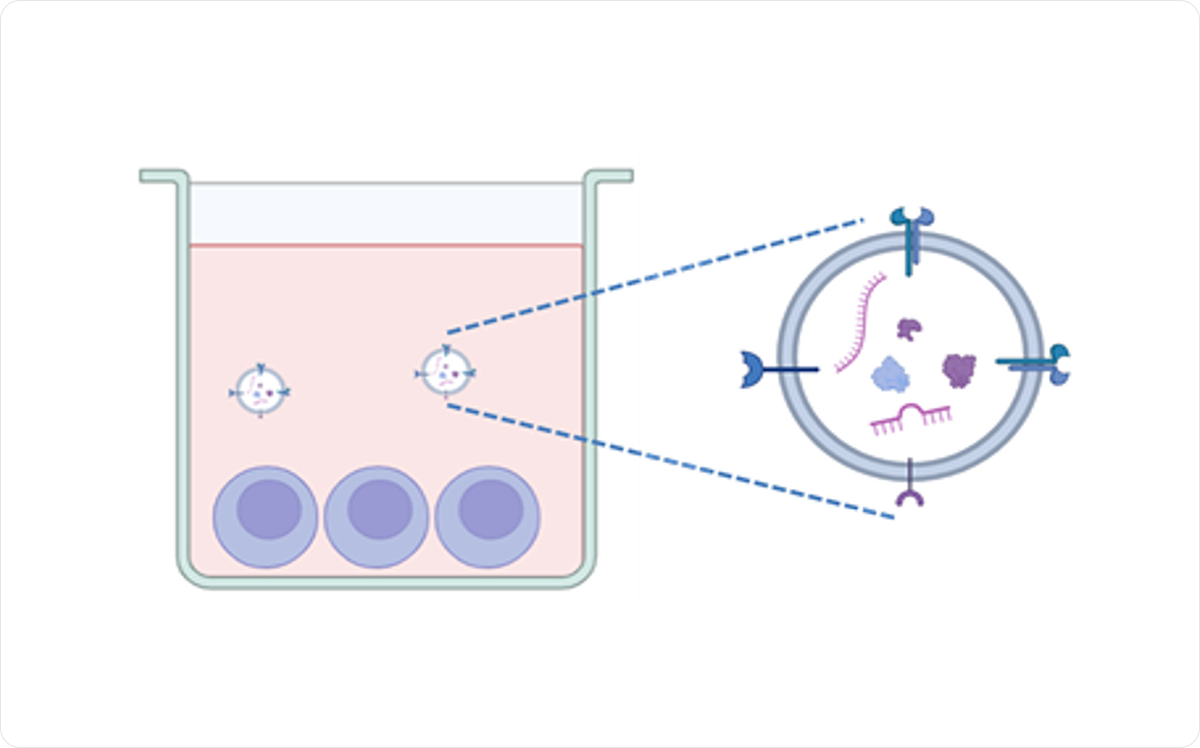

幹細胞上清液とは

- 幹細胞を培養した後に残る培養液を、遠心分離と滅菌処理を経て得られる上澄み液。

幹細胞上清液が注目される理由

- かつては廃棄されていた培養液に、サイトカインや多種多様な成長因子が豊富に含まれていることが判明。

- 幹細胞上清液の点滴投与により、細胞の分化促進、組織修復、機能回復が期待できる。